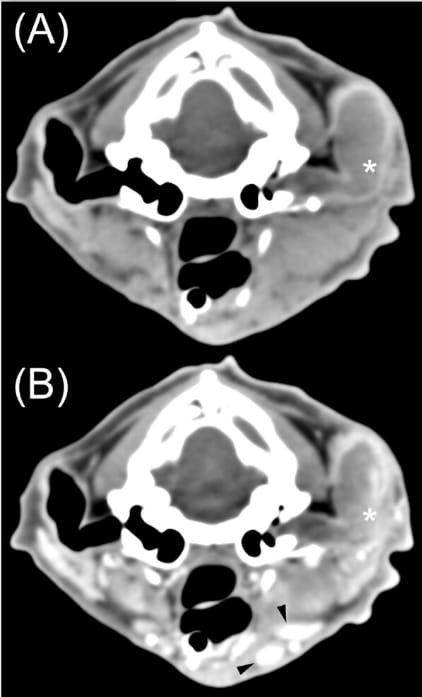

Twelve-year-old castrated male domestic shorthair with a malignant ceruminous neoplasm. A, Precontrast soft tissue transverse CT image. The left external ear canal is filled with soft tissue and fluid-attenuating material. B, Postcontrast soft tissue transverse CT image. This mass (asterisks) has homogeneous attenuation, moderate to marked, heterogeneous contrast enhancement, an irregular luminal margin, and shares a broad margin with the vertical ear canal wall.